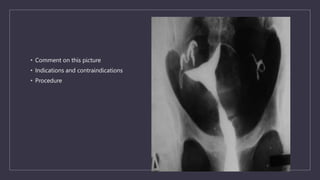

• Comment on this picture

• Indications and contraindications

• Procedure

Comment on this picture

How to manage..?

HSG findings in Genital TB

FALLOPIAN TUBES

Specific findings

• Beaded tube

• Golf club appearance

• Pipestem app

• Floral app

• Leopard skin app

Non specific findings

• Hydrosalphinx

• Mucosal thickening

• Peritubal adhesions(tobacco pouch app, loculated spill, cockscrew app